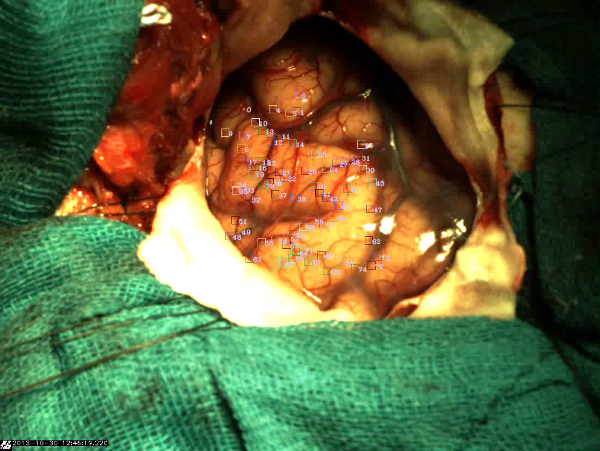

| Experimental setup of a deformable brain phantom for real-time modeling of intra-operative brain shift based on video tracking: (a) The whole phantom; (b) view through a mock craniotomy; (c) tracked features on a live brain. | ||